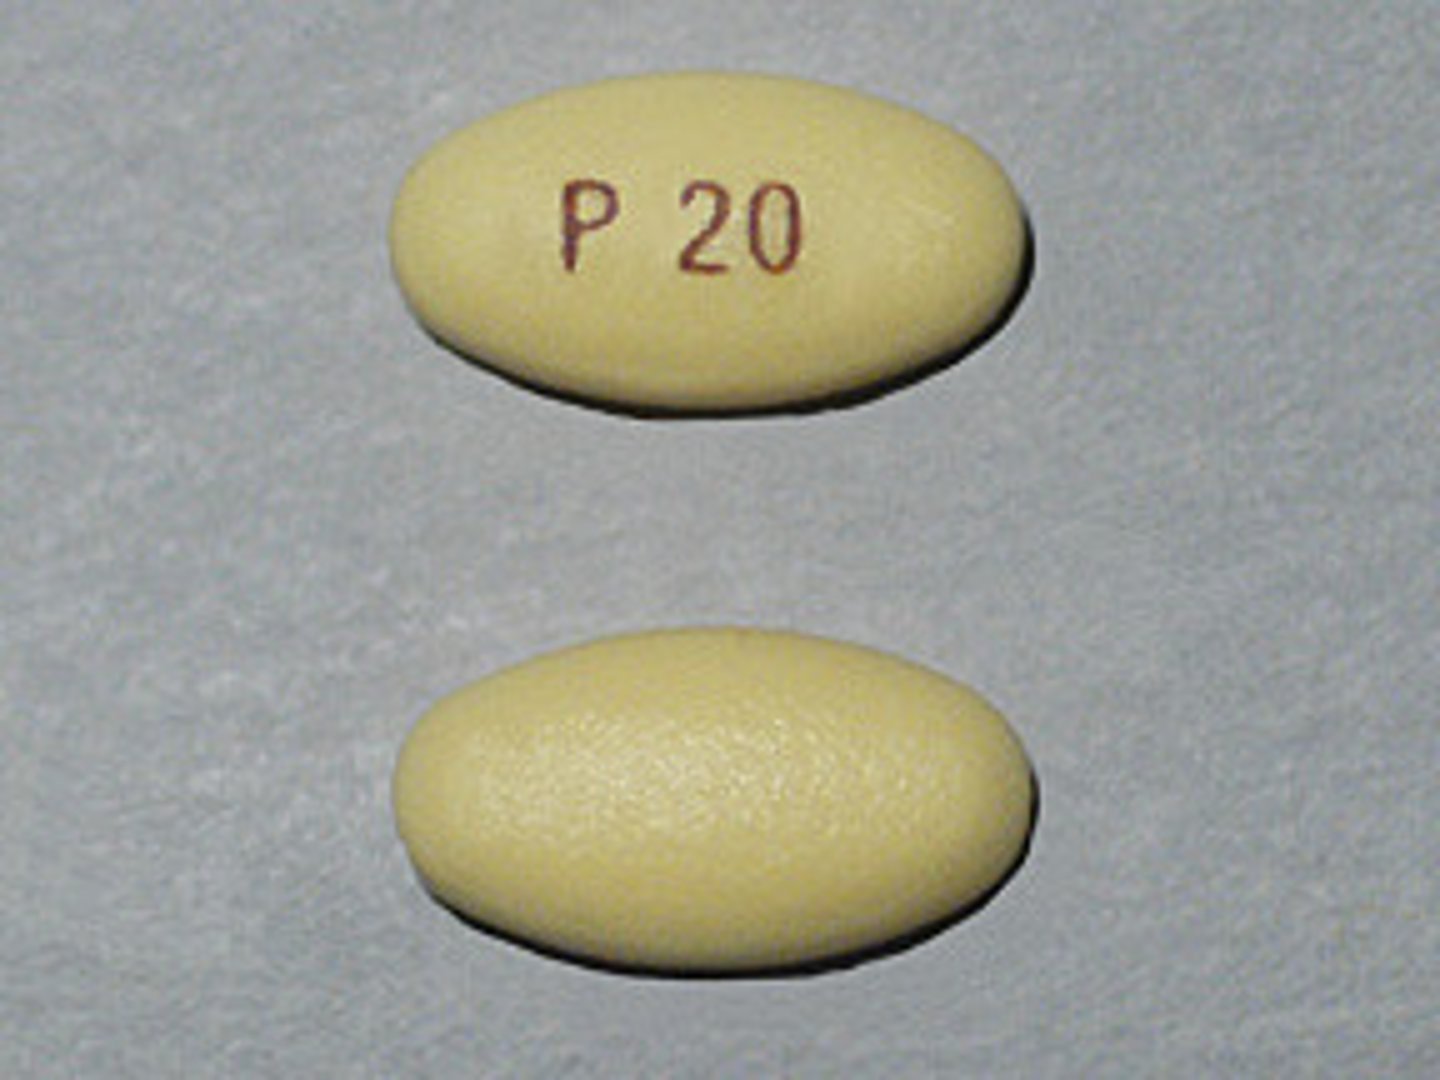

Pantoprazole Sodium

Brand: Protonix

Class: PPI

Drug Interaction: Can reduce effectiveness of clopidogrel

Indication: Acid-Reflux/GERD

Schedule: NCLM